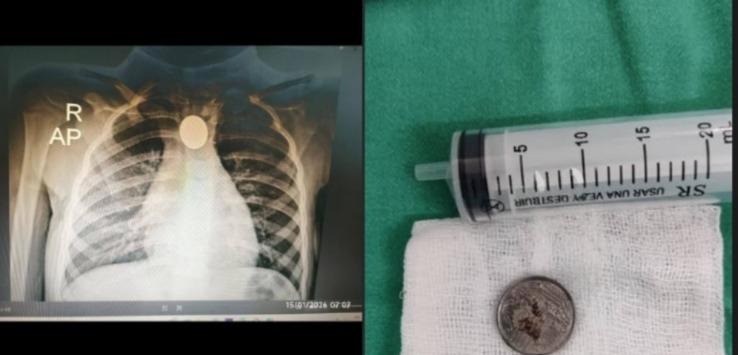

Una niña de 3 años fue asistida de urgencia tras presentar una moneda atascada en el esófago, situación que generó gran preocupación en su familia y en el personal médico que la atendía inicialmente en el Hospital de Mariano Roque Alonso.

Ya en el centro asistencial, el médico aplicó una técnica alternativa de extracción, aprendida y enseñada a su equipo de trabajo, logrando retirar con éxito la moneda y estabilizar a la menor, devolviendo la tranquilidad a sus familiares.

De acuerdo con lo explicado, existen dos procedimientos habituales para este tipo de casos: la endoscopía digestiva, realizada por un gastroenterólogo, y la esofagoscopía rígida, técnica para la cual el profesional fue entrenado. Sin embargo, en esta ocasión se optó por un método que permite resolver la urgencia con un médico entrenado y un anestesiólogo, incluso fuera de centros altamente especializados.

Para la intervención se utilizaron insumos básicos como sonda Foley, pinza McGill y laringoscopio, además de la sedación correspondiente, destacándose la coordinación del equipo médico y la rápida toma de decisiones.